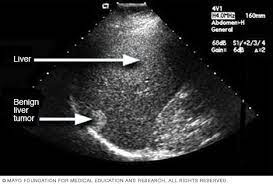

Most people don't have signs and symptoms in the early stages of primary liver cancer.

In addition to general malaise, below are 11 symptoms of liver cancer: The liver is a large organ and can function normally even with a large tumour. About the size of a football, it's located mainly in the upper right portion of your abdomen, beneath the diaphragm and above your stomach. Pain in the abdomen or shoulder pain is a common symptom for those with liver cancer. Other professionals are included as needed. It is to be noted that the symptoms of the liver cancer generally becomes clear in the stage 4. Other health conditions, including scarring of the liver (called cirrhosis. Robert key, a family medicine physician for mayo clinic health system, there are seven signs and symptoms that deserve immediate medical attention: Signs and symptoms of ovarian cancer may include: Most people don't have signs and symptoms in the early stages of primary liver cancer. Liver cancer will be cured for the small number of people who are able to have a successful organ transplant. Diagnosing pancreatic cancer early enough for effective treatment can be challenging for a number of reasons: Whether you or someone you love has cancer, knowing what to expect can help you cope.

According to the mayo clinic staff, other liver cancer symptoms include a yellow discoloration of the skin and the whites of your eyes (jaundice), white, chalky stools, general weakness, and fatigue.

The liver is your largest internal organ. Smoking is by far the most common cause of lung cancer. Liver cancer may not cause any signs or symptoms in its early stages. Other professionals are included as needed. Other health conditions, including scarring of the liver (called cirrhosis. See a doctor if you experience any symptoms or signs that worry you. About the size of a football, it's located mainly in the upper right portion of your abdomen, beneath the diaphragm and above your stomach. The most common liver cancer is hepatocellular carcinoma, as it forms in the main liver cell called the hepatocyte. The liver is a large organ and can function normally even with a large tumour. If the disease worsens, a liver transplant may be needed. People who smoke make up about 85 percent of lung cancer cases. If you go to your doctor when you first notice symptoms, your cancer might be diagnosed earlier, when treatment is most likely to be helpful. In addition to general malaise, below are 11 symptoms of liver cancer:

Symptoms signs and symptoms of cholangiocarcinoma include: Pancreatic cancer often doesn't cause any signs or symptoms in the early stages; Symptoms may include constipation or diarrhea, bloating, feeling full quickly when you eat, back pain, shortness of breath, or chest pain. Weight loss and lack of appetite. Liver cancer is a cancer that initiates in the cells of the organ and then spreads, according to mayo clinic.